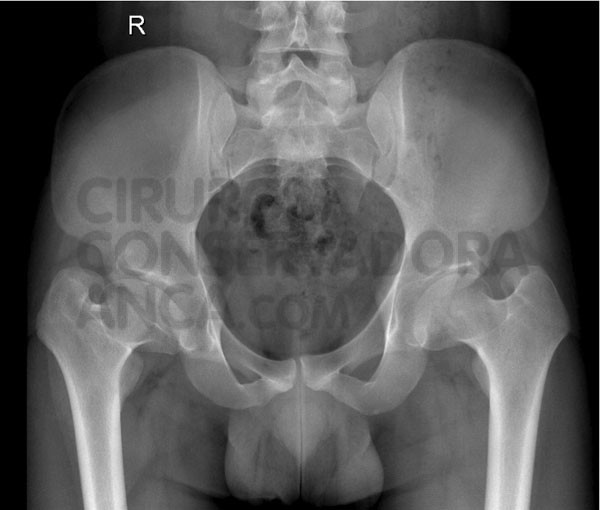

Anteroposterior Pelvis A Projection In A 32 Year Old Female With Download Scientific Diagram

Perthes Disease Hip Preserving Surgery